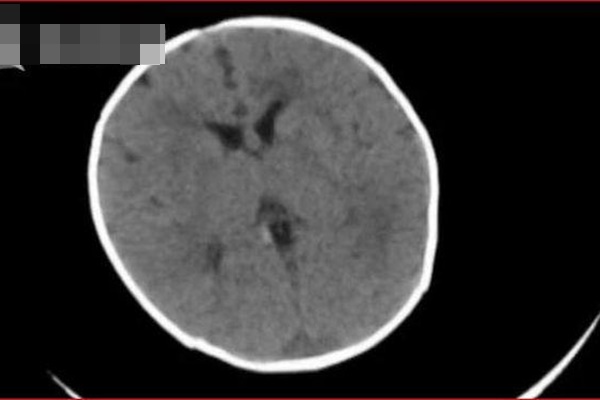

Sáng ngày 28/6, một học sinh 16 tuổi từ một trường trung học ở Tây An, Trung Quốc bị xuất huyết não trong quá trình chuẩn bị cho kỳ thi vào cấp 3 và được người thân đưa đến bệnh viện. Khi nhập viện, bệnh nhân bị hôn mê sâu, sau khi kiểm tra tại bệnh viện, chụp mạch máu não của bệnh nhân, bác sĩ phát hiện dị tật mạch máu não hiếm gặp, gây chảy máu rất lớn.

Sau đó, các bác sĩ lập tức cấp cứu, ngày hôm sau tình trạng sức khỏe của cậu bé đã được ổn định. Sau khi bệnh nhân tỉnh táo, bác sĩ Trần Hảo, Giám đốc Khoa não, Bệnh viện Y học Cổ truyền Trung Quốc Tây An nói rằng nguyên nhân sâu xa của xuất huyết não đột ngột của cậu bé là do dị tật mạch máu não. Áp lực của kỳ thi tuyển sinh, tâm trạng thay đổi, tâm lý thường xuyên bị kích thích, chất lượng giấc ngủ kém, chế độ ăn uống kém chính là tác nhân gây xuất huyết não.